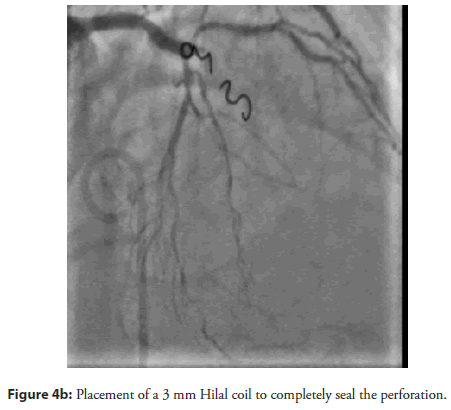

The patient and his family declined Coronary Artery Bypass Graft (CABG) surgery; therefore, the primary treatment strategy was to attempt revascularization of the LAD CTO lesion. An antegrade approach was selected, with the right femoral artery used as the primary access route and the right radial artery used for additional support. The initial attempts were made using Fielder XT, Fielder XT-R, and Gaia Next 2 guide wires (Figure 2a–Figure 2c). However, the Caravel microcatheter could not be advanced across the tight lesion. Therefore, predilatation was attempted using a 1.25 × 10 mm balloon followed by a 2 × 12 mm Non-Compliant (NC) balloon. Unfortunately, the wire was found to be in a false tract, which resulted in a Type III LAD perforation with subsequent cardiac tamponade. Emergency pericardiocentesis was performed (Figure 3a, Figure 3b). The LAD perforation was successfully sealed using 2 mm and 3 mm Hilal coils (Figure 4a–Figure 4c).

Figure 3a: Coronary angiography demonstrating Type III LAD perforation.